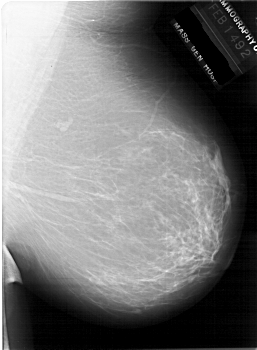

A_1940_1.LEFT_CC

LEFT_CC LINES 6436 PIXELS_PER_LINE 4786 BITS_PER_PIXEL 12 RESOLUTION 43.5 OVERLAY